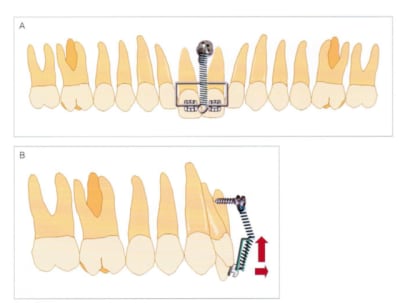

si l'ingression de la 11 est toujours d'actualité ci joint un dispositif a appliquer uniquement sur la 11.

vous aurez besoin d'un bout de fil 19*25 acier

et une minivis.

refrence:

Clinical Application of Orthodontic Mini-implant

Tae-Woo Kim DDS, MSD, PHD

Attention dans le cas présenter par inset il s'agit d'une class II division II dans ce cas on veut obtenir une protrusion des incisives centrales donc le dispositif est parfaitement adapté.

Pour ingresser la dent tu fait juste un pliage du type sur le dessins.

SI la dent procline tu plie le fil en lingual.